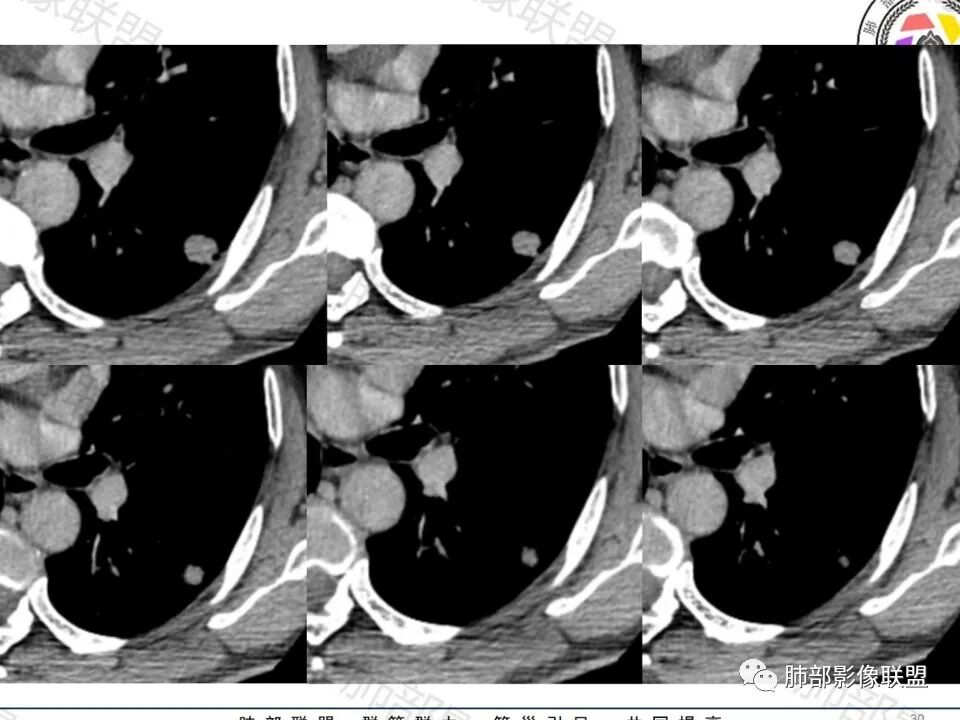

左肺下叶胸膜下实性小结节,边缘可见毛刺,轻度收缩,近端与血管束相连,远端轻度牵拉胸膜,并远端可见小空泡,平扫密度均匀,增强后渐近性强化,考虑腺癌,鉴别隐球菌

许慧良:

中老年男性患者,无症状体检发现,胸部CT:左下肺内前基底段近胸膜下类圆形结节,边缘清晰,周围晕征,周围毛刺细软,有胸膜牵拉及血管进入,增强扫描明显不均匀强化,考虑炎性肉芽肿,隐球菌可能,鉴别腺癌

傅昌瑜:

晨读:左肺下叶胸膜下实性小结节,边缘可见模糊晕及毛刺,轻度收缩,与支气管关系不清,近端与血管束相连,内见小空泡,平扫密度均匀,均匀强化。远近可见多个小结节。考虑炎性肉芽肿,隐球菌病,鉴别结核、腺癌。

增强的程度很难讲,但是不均匀强化是可以确定的;